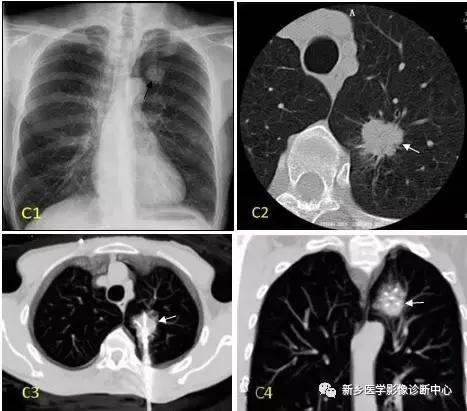

肺癌

多发生于年纪较大50Y以上,多有咳嗽,咯血,胸痛,发热等症状。以上肺多见,中下肺次之。密度均匀或不均匀的结节病灶,分叶,界清,短毛刺,可有空泡征,偏心空洞、兔儿征等,一般无钙化。

结核球

好发于年轻人,早期临床不明显。好发于锁骨下区,一般右侧多于左侧。类圆形结节致密影,边缘清楚,密度均匀或不均,可有钙化,周围常有细斑点及条索影等卫星病灶。

支气管囊肿(单发)

年轻人30Y多发,无明显症状或有咳嗽,发热,胸痛,脓性痰等。以下肺野内带常见。类圆形水样密度影,无钙化,一般在10HU以下,含粘液时CT值增高,可与支气管相通成为含气囊肿。